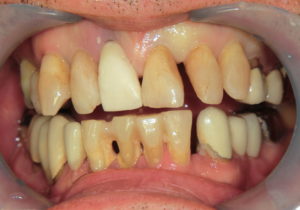

歯ぐきの腫れで最も多い原因として挙げられるのが歯周病です。

歯周病の初期症状は歯肉の腫れや出血です。

放置すると歯を支える歯槽骨が溶け、それに伴って歯周ポケットが深くなります。

歯周ポケットが深くなると歯の周りに細菌がたくさん溜まってしまうので、歯ぐきが化膿して腫れやすくなります。